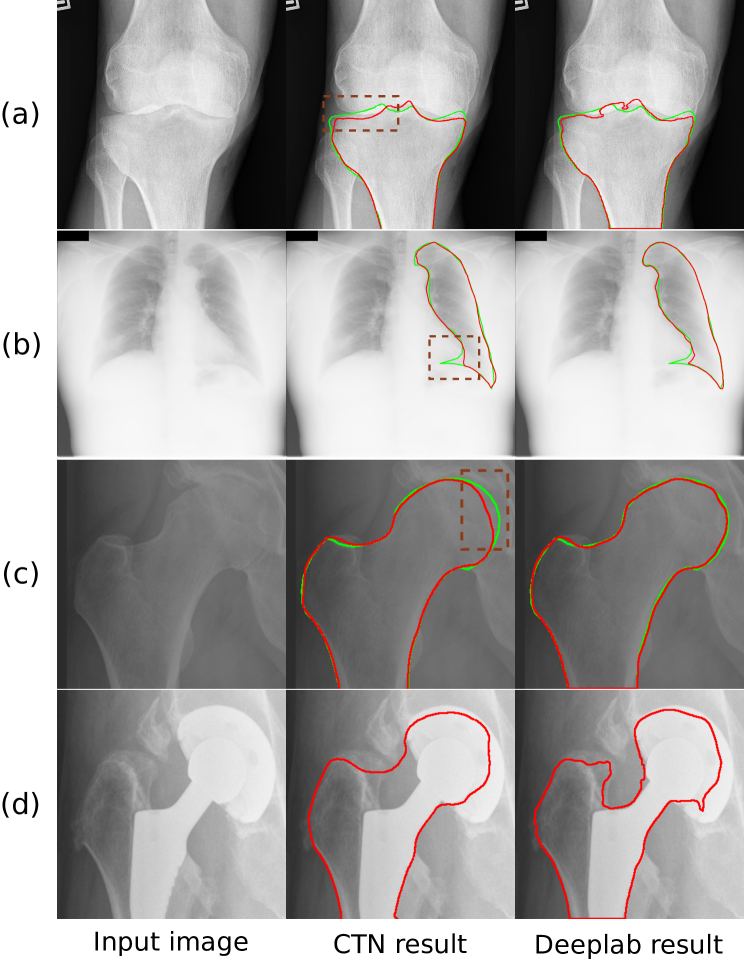

Fig. 5: Segmentation results of four example images. The boundaries of ground truth segmentations (the green lines) are drawn for comparison.

We compare CTN against seven representative methods from three categories: non-learning-based, one-shot, and fully supervised segmentation methods. The quantitative results are reported in Table 1 and visualizations of segmentation results are shown in Fig. 5.

The results in Table 1 show that our method significantly outperforms both MorphACWE and MorphGAC. Specifically, on average we achieve 15.63% higher IoU and 20.94 pixels less HD than MorphGAC, the better of the two. The visualizations of segmentation results in Fig. 5 confirm that these two approaches cannot provide satisfactory segmentation accuracy, especially when the boundary of such structures is not clear, e.g., lung segmentation. We posit that the inferior performance of ACM-based methods is owing to two factors: 1) the gradient-based energy function is not suitable for objects without clear boundary, 2) optimizing the energy function on single image often encounters local minima (i.e., causing segmentation leakage). In contrast, CTN optimizes shape and appearance-based loss functions on an aggregated of the unlabeled dataset to achieve high robustness. Fig. 6 shows the evolution process of the CTN contour on a phalanx image.

As shown in Table 1, CANet achieves only 48.98% IoU on average. We speculate that the poor performance is caused by the domain gap between natural images and medical images. Brainstorm achieves better performances with an average IoU and HD of 82.46% and 36.71, respectively. This is still significantly lower than CTN, of which the average IoU and HD are 96.58% and 8.66, respectively. Fig. 5 shows that while Brainstorm is able to segment the object’s overall structure, it has low accuracy on the segmentation boundaries.

CTN trained with only one exemplar performs comparably with the fully supervised UNet, and slightly falls behind DeepLab, the best of the baseline methods, by 0.58% in IoU and 1.41 pixel in HD, respectively. These results suggest that with only one exemplar, CTN can compete head-to-head with very strong fully supervised baselines. We note that since these fully supervised methods predict segmentation labels at pixel-level, the topology of the segmentation is not guaranteed, e.g., small isolated lung masks in Fig. 5. In contrast, CTN is able to retain the topology. Moreover, we will demonstrate in Section 3.3 that with minimal human feedback, CTN can even outperform fully supervised models.